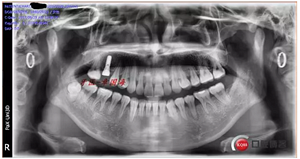

種植后圖片:

完成。